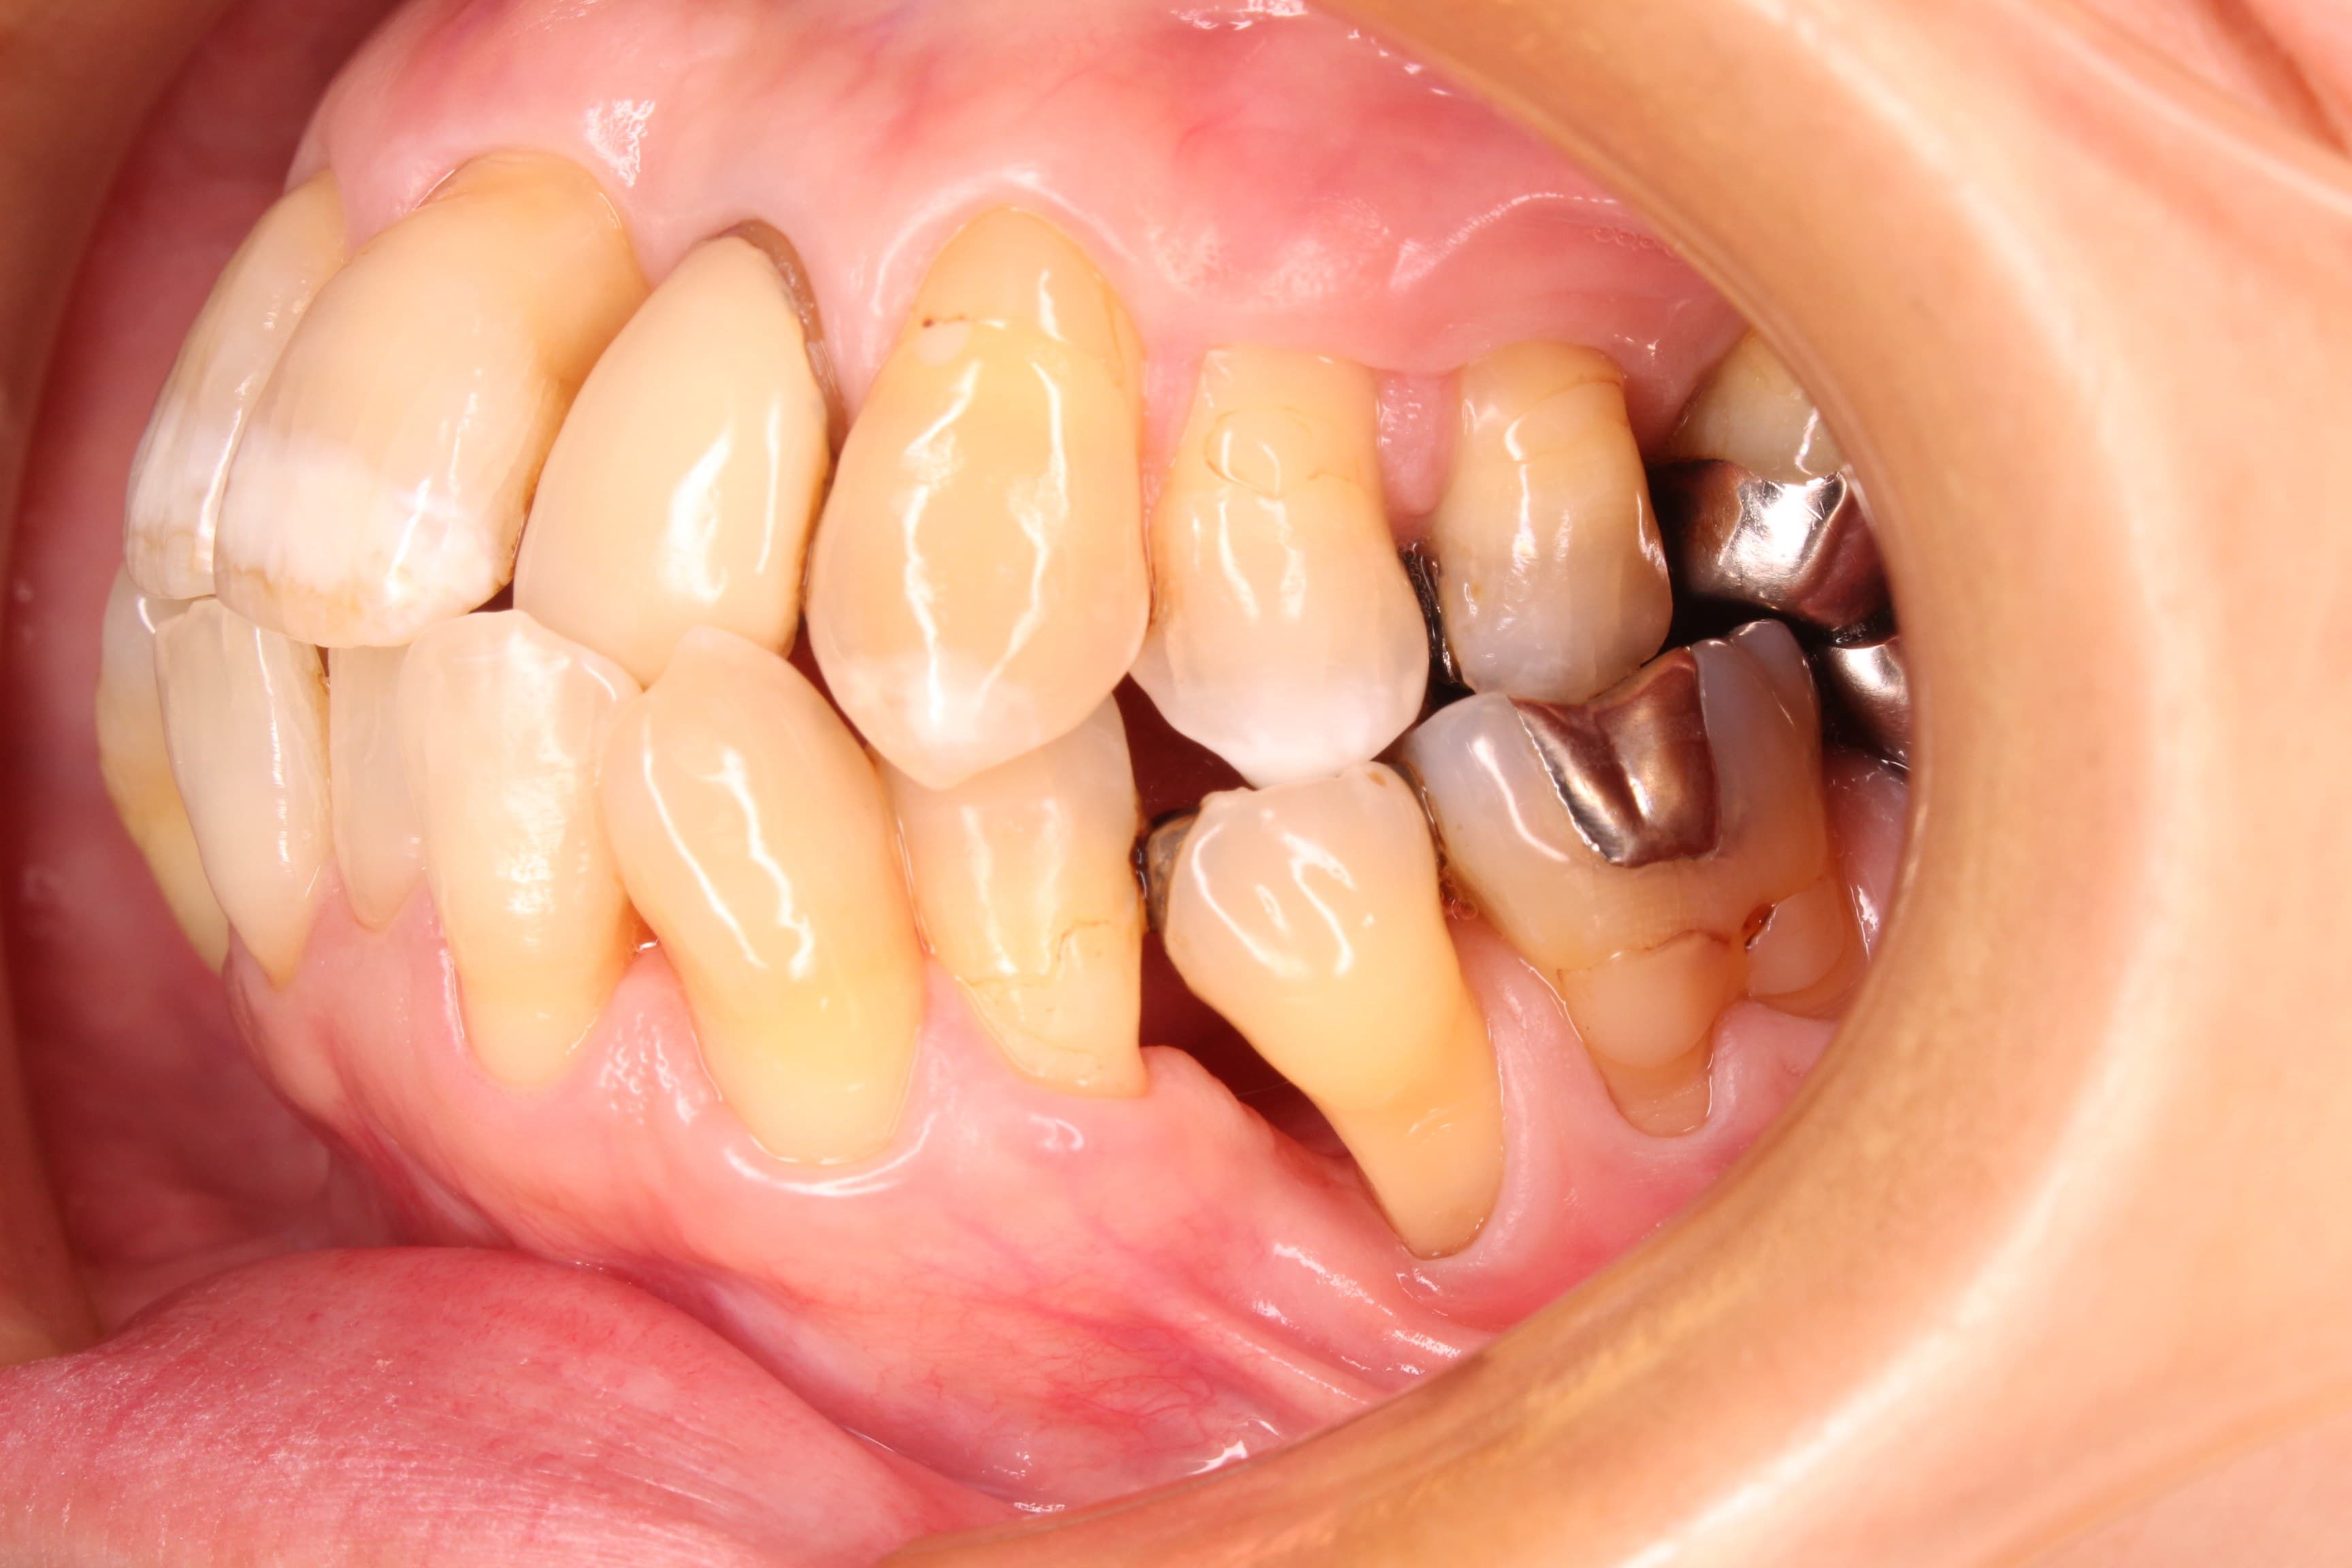

<治療後>

「定期検診に行くことは、健康な状態を維持するためにとても重要な事です。」

定期健診では、バイオフィルムというブラシでは落とせない細菌を落としていきます。

また、ブラッシングは365日×3回行うので、とても重要な役割を担っています。

定期健診が終わったあと24時間後には病原菌は増殖し始めるので、それを毎日綺麗に落とすことが

健康な状態を維持するためには大切です。

ただ、病気が治っていない状態での定期検診はあまり意味がありません。

病気があるなら、まずは適切に治療をして健康な状態に回復してから定期検診を受ける必要があります。